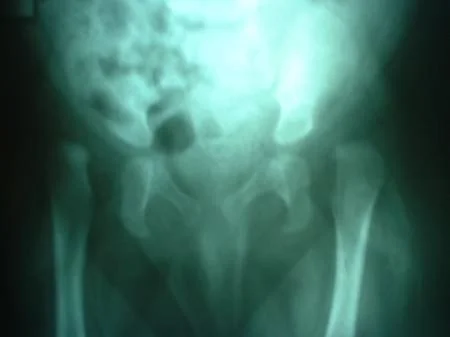

La Displasia del Desarrollo de la Cadera ó Displasia Evolutiva de la Cadera, es un problema dinámico que abarca un amplio espectro de condiciones patológicas, clínicas y radiológicas, que incluyen desde  la cadera luxada, subluxa y la inestable, pasando por la displasia o alteración del desarrollo acetabular o de la cabeza del fémur. Ver más.